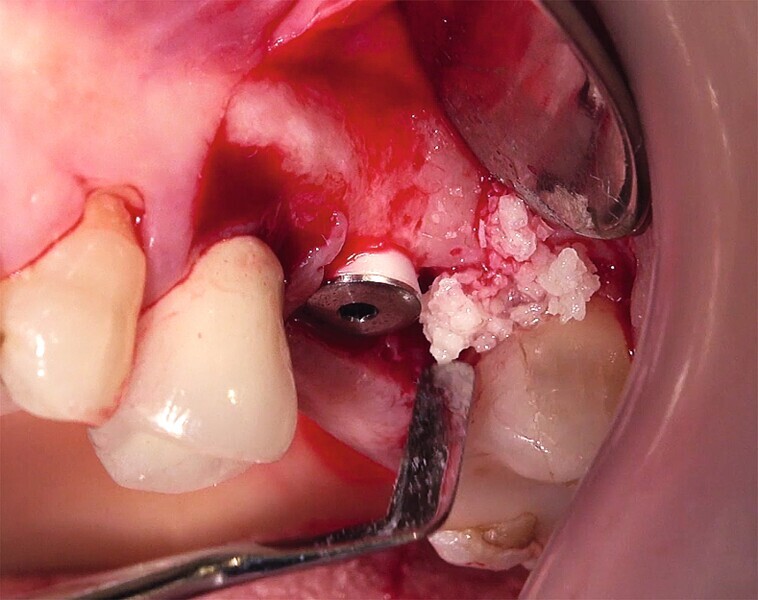

Fig. 29 : Augmentation osseuse latérale (régénération osseuse guidée) au moyen d’une allogreffe constituée d’un substitut osseux, simultanément à la pose des implants.

Fig. 30 : Augmentation osseuse latérale (régénération osseuse guidée) au moyen d’une allogreffe constituée d’un substitut osseux, simultanément à la pose des implants.

La crête alvéolaire au niveau du site de la molaire inférieure était trop étroite pour permettre la pose prédictible d’un implant sans une augmentation osseuse préalable. Des implants deux pièces en zircone ont été mis en place, simultanément à une augmentation osseuse latérale, au moyen d’une allogreffe et d’une membrane de collagène résorbable (Figs. 25–34).